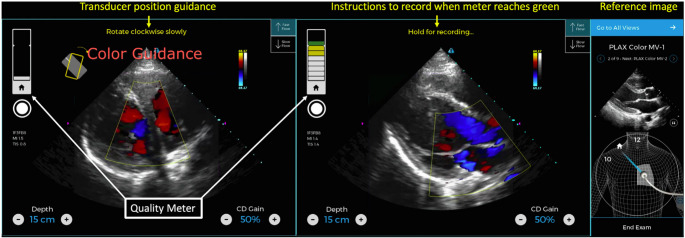

Purpose of review: The integration of artificial intelligence (AI) with point-of-care ultrasound (POCUS) is transforming cardiovascular diagnostics by enhancing image acquisition, interpretation, and workflow efficiency. These advancements hold promise in expanding access to cardiovascular imaging in resource-limited settings and enabling early disease detection through screening applications. This review explores the opportunities and challenges of AI-enabled POCUS as it reshapes the landscape of cardiovascular imaging.

Recent findings: AI-enabled systems can reduce operator dependency, improve image quality, and support clinicians-both novice and experienced-in capturing diagnostically valuable images, ultimately promoting consistency across diverse clinical environments. However, widespread adoption faces significant challenges, including concerns around algorithm generalizability, bias, explainability, clinician trust, and data privacy. Addressing these issues through standardized development, ethical oversight, and clinician-AI collaboration will be critical to safe and effective implementation. Looking ahead, emerging innovations-such as autonomous scanning, real-time predictive analytics, tele-ultrasound, and patient-performed imaging-underscore the transformative potential of AI-enabled POCUS in reshaping cardiovascular care and advancing equitable healthcare delivery worldwide.